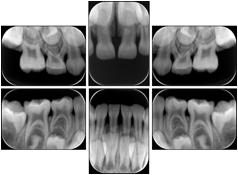

3. A dental provider wishes to capture a series of DICOM IO images for the patient’s dentition. The tooth morphology, teeth are divided into molars, premolars, canines and incisors, and a number of images for each jaw. The anatomic information was captured utilizing the triplet of schema. This standard code sequence is based on ISO 3950-2010, Dentistry - Designation system for teeth and areas of the oral cavity.

Every IO image should have anatomic information either through the primary or modifier sequence.

In most standard cases, images are oriented in structured layouts. These structured displays are useful to be shared between providers for reference purposes.

Table OO.1.1-1 shows structured display standard templates, where Viewset ID is based on the Japanese Society for Oral and Maxillofacial Radiology (JSOMR) classification provided by JIRA (Japan Medical Imaging and Radiological Systems Industries Association, www.jira-net.or.jp). Expected or typical teeth to be imaged location, region and designation codes are based on ISO 3950-2010, Dentistry - Designation system for teeth and areas of the oral cavity. For all the hanging protocols listed in OO.1.1-1, the value to use for Hanging Protocol Creator (0072,0008) is "JSOMR" and the value to use for Hanging Protocol Name (0072,0002) does not include "JSOMR" (e.g., "DL-S001A", not "JSOMR DL-S001A").